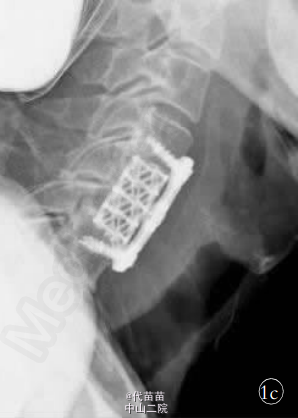

患者,男,61岁。 因高处坠落致颈部疼痛 2h余入院。 查体:C4-C6棘突压痛明显,活动受限,稍有肿胀,双上肢感觉麻木伴有痛觉过敏,双侧肱二头肌肌力Ⅳ级,双手握力下降,双下肢感觉活动可,肢端感觉血供可。入院时实验室检查均未见明显异常。 MRI 检查显示 C3-C7 椎间盘后突伴 C4-C6 平面椎管狭窄,颈髓受压,髓内见小片高信号影,颈椎退行性改变(图1a)。 诊断:①颈椎病;②颈髓损伤。 手术:采用全身麻醉,取颈部右侧斜行切口,长约 6 cm,逐层切开皮肤、颈阔肌,沿气管食管与胸锁乳突肌、颈动静脉鞘间隙分离暴露椎前筋膜,分离椎体前筋膜,摄定位X线片,将前纵韧带切开,显露病变椎体及椎间盘, 先用角度刮匙和髓核钳切除病变段椎间盘及上下 终板,用高速磨钻行病变椎体大部分切除,显露硬脊膜和致压物。 小心分离致压物,彻底解除脊髓压迫。 植入大小适中填满松质骨的钛网, 再将长短合适的颈前路钢板系统通过螺丝钉固定于开槽减压区上下方椎体上。 C 形臂 X 线机透视证实钢板系统位置正确后,切口内置负压引流管,逐层缝合切口。 手术顺利,出血约 200 ml。 术后 48 h 切口引流量约 50 ml,拔除引流管。术后复查 X 线片示内固定位置可(图 1b,1c)。术后查体:双上肢感觉无麻木,双侧肱二头肌肌力Ⅳ级强,双手握力Ⅳ级,双下肢各肌群肌力Ⅴ级,感觉活动可。 术后第 5 天突发神志不清 ,躁动不安 ,查体 :双上肢肌 力Ⅲ级 ,双 下 肢 肌 力0 级,病理反射未引出。 急查头颅 CT、血电解质、血气分析等 均未发现明显异常, 胸部 CT 示双肺下叶炎症伴两侧胸膜反应。 经相关临床科室会诊后转入 ICU 监护,予抗感染,加强龙冲击等对症支持治疗。复查头颅 MRI、DWI、MRA,胸腰椎 MRI均未见明显异常, 颈椎 MRI 示:C4-C6 椎体内固定术后改变,颈髓受压,髓内见小片高信号影(图 1d)。 经外院脊柱外科专家会诊: 颈髓受压影像考虑为内固定产生伪影所致。 术后第10 天,患者情况较前明显好转,转入我科继续抗感染、营养神经、针灸等对症治疗。 查体:神志清,切口愈合良好,平乳头平面以下感觉麻木,双侧肱二头肌肌力Ⅲ级,双下肢股四头肌肌力Ⅰ级,双侧胫前肌、拇长伸肌肌力 0 级,巴彬斯基征阳性,奥本汉姆征阳性。 术后 15 d 双下肢股四头肌、胫前肌肌力较前出现好转。 术后 20 d 双下肢肌群肌力恢复至Ⅲ级水平。 术后45d双上肢肌群肌力Ⅴ级,双下肢肌群肌力Ⅵ级强,已下地步行训练。 近年来, 颈椎前路减压植骨钢板螺钉内固定术已普遍运用于颈椎疾病的治疗中,然而手术后并发症也时有发生。本例患者术后近 1 周突发下肢截瘫,1 个月后又基本恢复,实属罕见。 分析原因:①考虑术后血肿形成,压迫脊髓造成相应症状出现。②考虑内植物松动移位。 ③可能与术后感染,脓肿压迫神经组织有关。 然而标准的颈前路手术有 1%~3% 的创口感染率。本例患者术后切口愈合良好,无红肿及液性渗出,颈椎 MRI 检查未见明显脓肿形成。 虽有肺部感染情况发生,但不足以构成对神经系统的损伤,导致截瘫的发生。 仔细回顾病史,患者曾有长年酗酒史,术后出现过意识 模糊,并伴有全身抽搐现象,复查电解质示血钙、血钠有异常,这与截瘫的发生不无关系。 有研究表明,对于长期酗酒患者,酒精戒断容易出现神经及精神方面症状。 而戒断性癫痫发作好发于长期饮酒后造成慢性酒精中毒的男性, 包括老年人在内的各年龄段都有可能发生,可无潜在的异常放电病灶,即头颅 MRI 或 CT检查未见明显异常。本例患者头颅相关检查并无异常,但电解质出现紊乱,且伴有高热、肺炎症状,加之以往有酗酒史,戒断综合征是不得不考虑的原因之一。 患者尽管已行前路钢板内固定,但颈椎的承受力远远未达到生理功能的要求,强烈的全身抽搐极有可能造成对颈髓的损伤,造成难以预计的后果。但神奇的是在截瘫后 1 月余,患者又逐渐恢复正常。查阅相关文献,尚未见有相关类似的报道。 对于此类患者,术前需仔细询问既往史,特别是酗酒史,防止戒断综合征的产生,术后加强监护,加强营养神经等对症支持治疗。